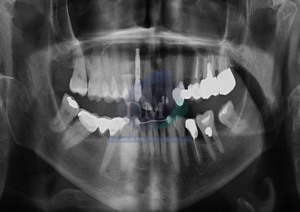

Paciente masculino de 52 años, es referido al Instituto de Diagnóstico Maxilofacial –IDM (Sede Surco) para evaluación de dolor en segundo cuadrante. Radiografia Panorámica En